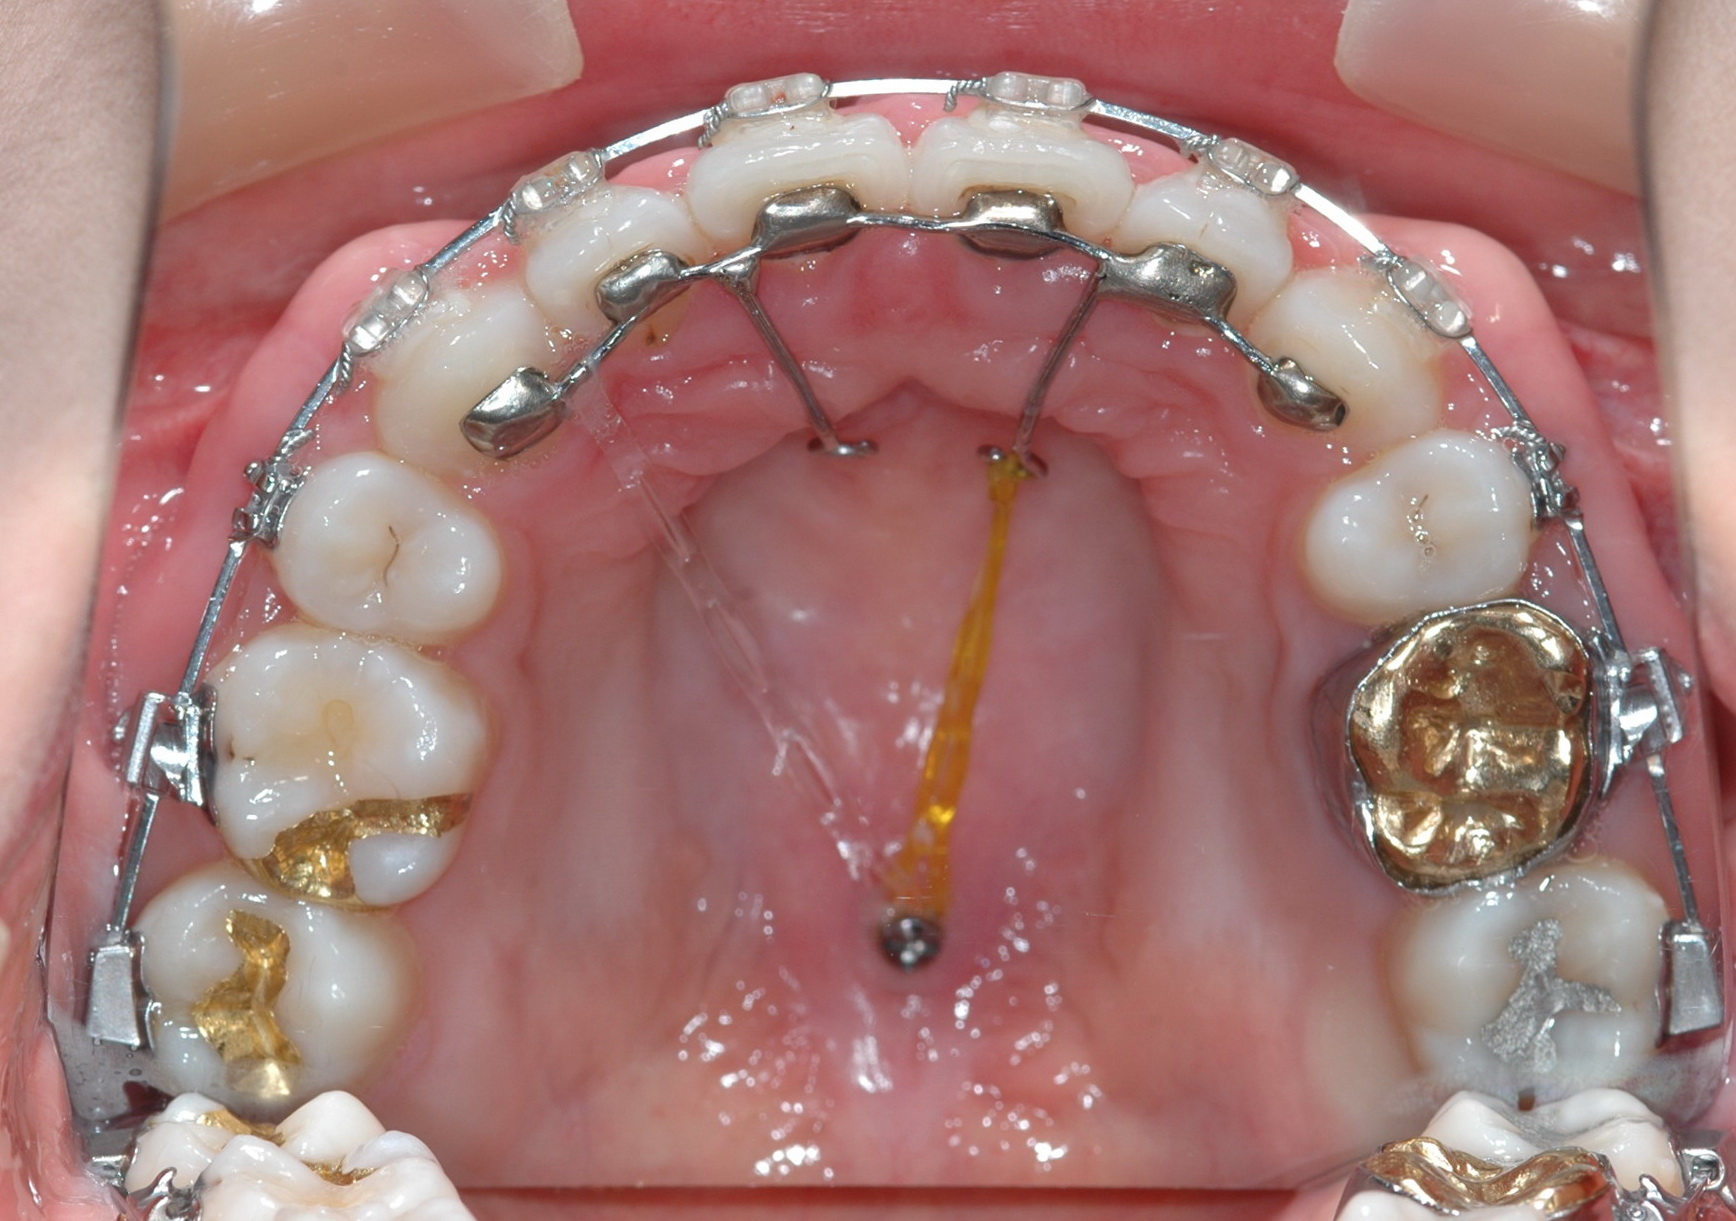

잇몸뼈 돌출인 경우에는 그림의 잇몸뼈를 넣는 교정치료를 하시면 됩니다. 그림과 같은 장치를 쓰면 치아 보다는 잇몸뼈가 주로 들어가게되는 장치입니다. 그러나 진단 시에 너무 심하게 윗턱이 나온 경우에는 수술도 고려해야합니다